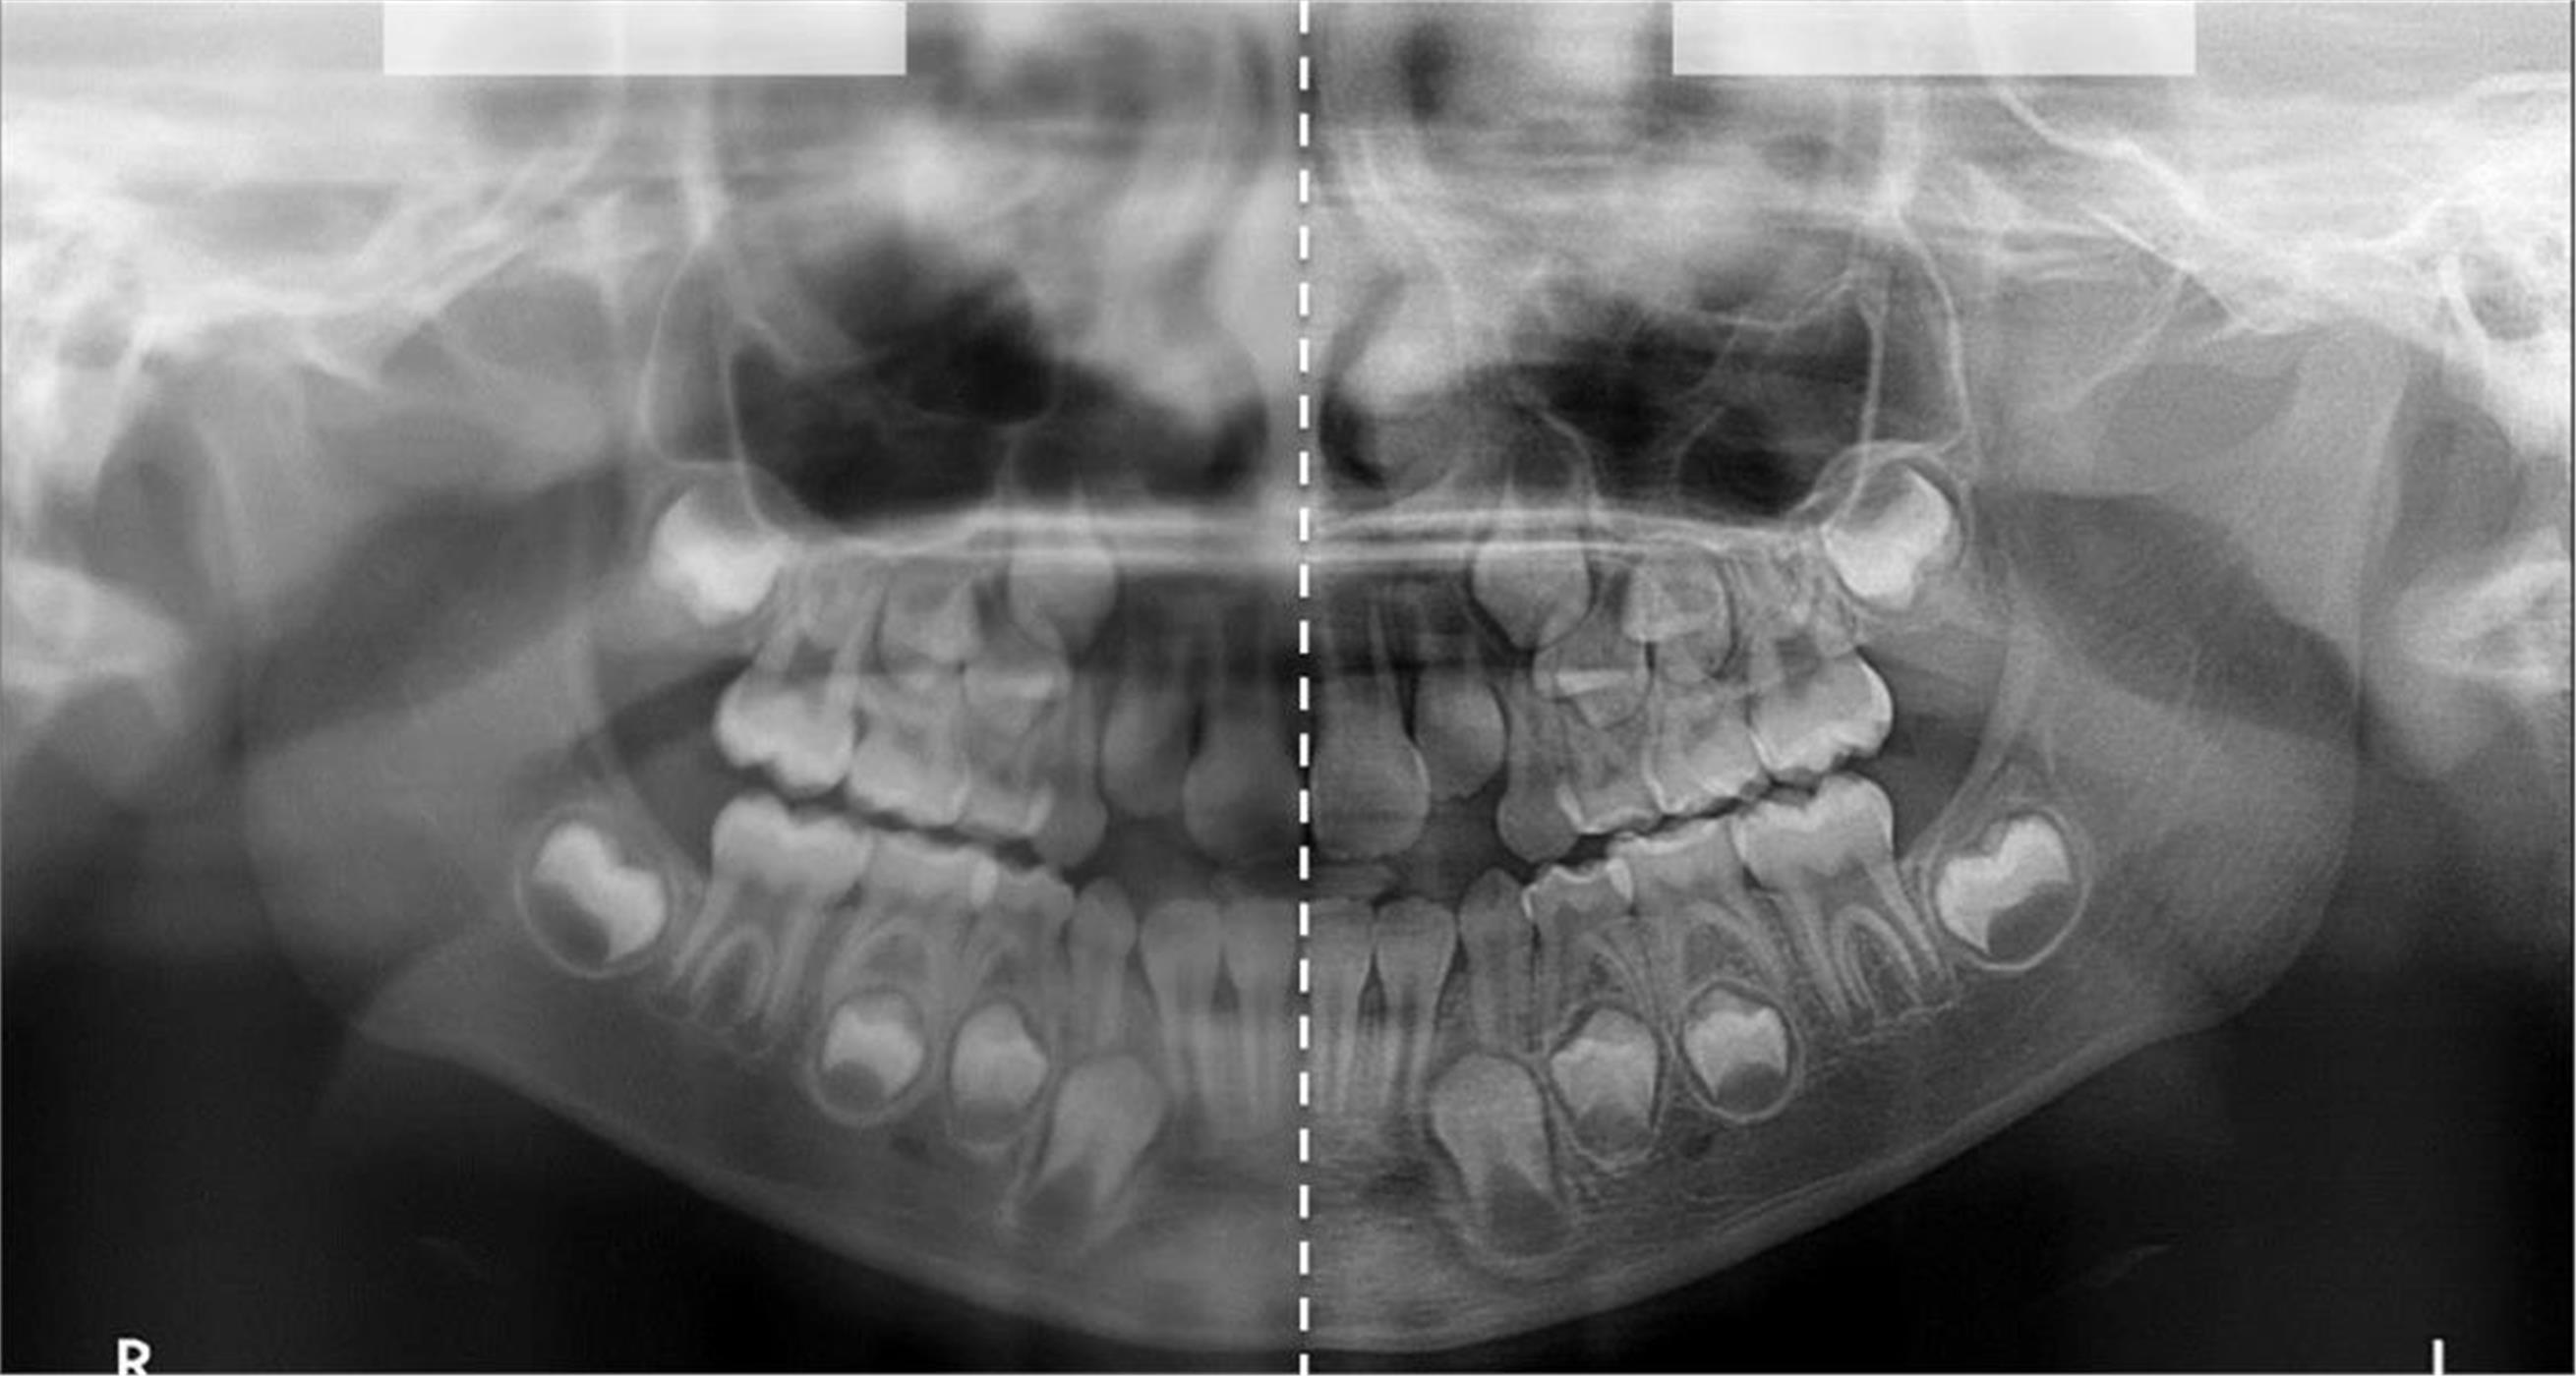

За само 13 секунди се добива високо квалитетна ортопантомграфска снимка, странична смнимка, снимка на вилични зглобови, снимка на синуси. Најновиот Kodak панорамикс има 2Д+ програма со која се добиваат 5 пресека во длабочина за прецизна дијагноза и позиција на импактирани заби и други промени. Со квалитетна панорамска снимка нашиот стручен тим ќе постави точна дијагноза и одреди соодветен план на терапија.